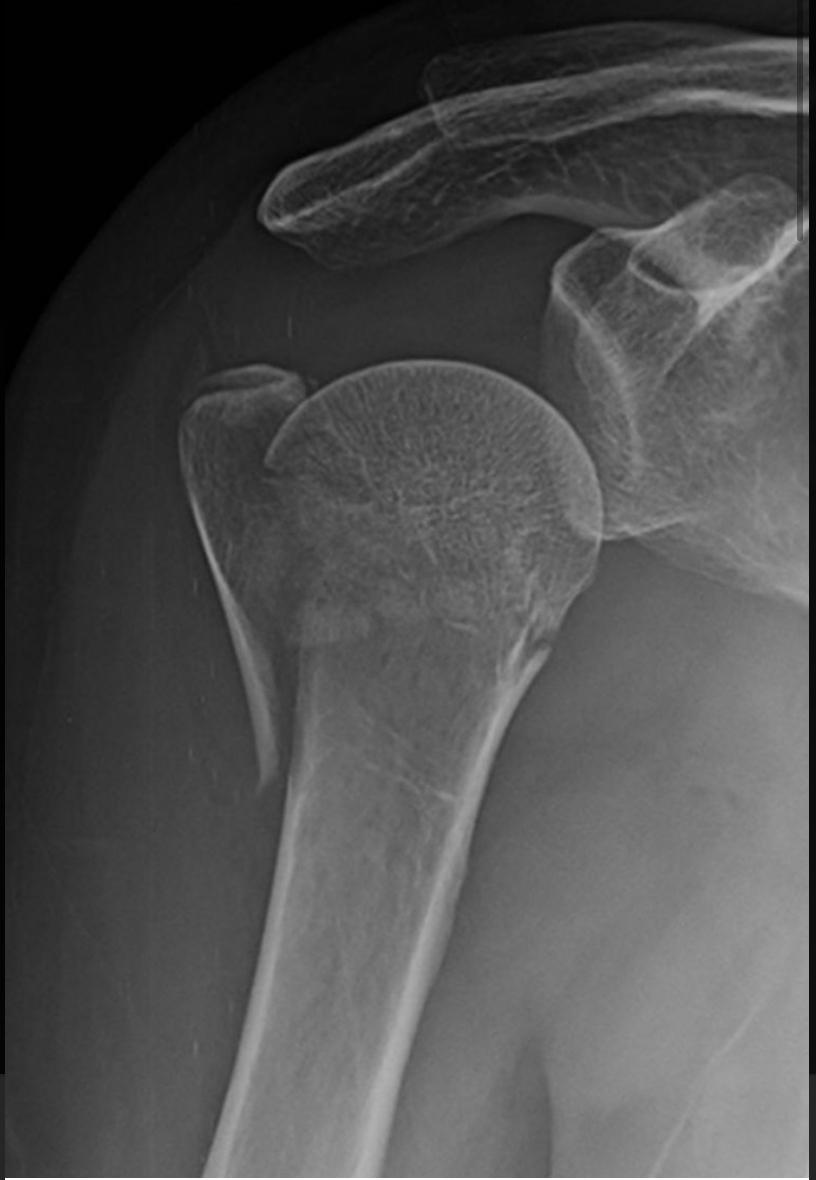

LUXAÇAO DO OMBRO

A luxação do ombro é a perda de contato dos ossos que compõe essa articulação, no caso o úmero e a escapular. Por ser a articulação do corpo humano com maior arco de movimento ela é mais suscetível a luxação, sendo a articulação mais deslocada no adulto. As principais causas da luxação são traumas no ombro ou então por frouxidão ligamentar. Radiografia é o primeiro exame a ser solicitado para se confirmar a lesão. Outros exames como a tomografia e a ressonância também são solicitados para a investigação de outras lesões. O tratamento imediato e a recolocação do ombro no lugar, através de manobras específicas. Alguns pacientes podem evoluir para um quadro de luxação recorrente do ombro, no qual a articulação pode sair do lugar com movimentos simples do dia a dia. Nessas situações o tratamento mais provável é o cirúrgico. O procedimento realizado na grande maioria das vezes é a artroscopia do ombro, entretanto alguns casos podem necessitar de cirurgia aberta ,